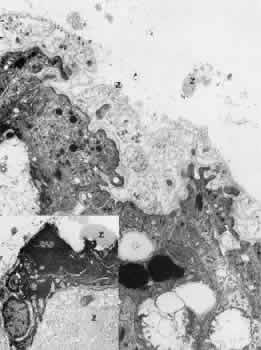

By light microscopy, zonular fiber bundles are eosinophilic, PAS-positive structures, often appearing to be ribbons connected by a paler interbundle “membrane” (Fig. 6). By scanning electron microscopy, the ribbons appear as groups of striated fiber bundles held together by a loose fibrogranular meshwork. Each fiber is composed of fibrils 10 nm in diameter, highly oriented and closely aggregated. Ultrastructurally, these fibrils have a tubular profile in cross section and a microperiodicity of 12 to14 nm seen along the fibril (Fig. 7). Dyes that precipitate and bind to polysaccharides show irregular granules and rod-like associated material on and between the fibrils.

Fig. 6. By scanning electron microscopy the ribbons of fiber bundles appear striated (× 2,200). Inset A. The flat ribbons of zonular bundles have a paler-staining “membrane” holding them together (arrow) (H&E, × 220). Inset B. The fibers are composed of highly oriented and tightly aggregated fibrils (× 23,000).